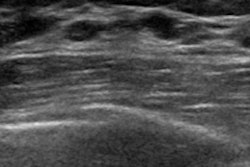

Ultrasound appears to be an effective and safe diagnostic workup modality when it comes to evaluating masses identified on screening digital breast tomosynthesis (DBT), according to research published in the European Journal of Radiology (EJR).

The findings suggest that, at least in the case of breast masses, it may not be necessary for women to undergo both digital mammography and ultrasound after screening DBT -- which has the benefit of reducing radiation exposure, wrote a group led by Dr. Jessica Porembka of the University of Texas Southwestern Medical Center in Dallas.

The researchers found that ultrasound alone was used in 69% of workups of recalled masses, and that the odds of masses being worked up with ultrasound alone was eight times that of the odds of digital mammography and ultrasound being used. The authors also found that "ultrasound alone in the diagnostic evaluation of a mass seen on screening DBT had a higher yield of true lesions than masses worked up with digital mammography/ultrasound," confirming that "masses seen on screening DBT can be adequately evaluated with ultrasound alone."